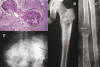

El tamaño del tumor oscila entre 2 y 13 cm y macroscópicamente muestra un tejido blando pero de textura arenosa que puede contener áreas quísticas. Histológicamente el tumor muestra un patrón lobular en visión panorámica. Las células neoplásicas tienen característicamente un citoplasma claro y membranas citoplásmicas bien definidas (fig. 7). Algunas células pueden mostrar un citoplasma rosado asemejándose a las células del condroblastoma. Ambos tipos de células son inmunohistoquímicamente intensamente positivas para la proteína S100. Las mitosis son muy infrecuentes (22).

Fig. 7: Condrosarcoma de células claras. A) Rx simple: AP de cadera derecha. Se observa lesión lítica localizada en la cabeza y el cuello femoral con fractura patológica. B) Visión panorámica microscópica del tumor en la que se reconoce ya a este pequeño aumento la abundancia de células de citoplasma claro (x15, HE). C) Detalle que muestra focos de cartílago hialino del tumor rodeados por células neoplásicas de citoplasma claro. D) Trabéculas de osteoide rodeadas por células neoplásicas de citoplasma claro. En C) y D) también se encuentran células gigantes de tipo osteoclástico (x90, HE).

Condrosarcoma de células claras. Ha sido definido como un raro condrosarcoma de bajo grado que se localiza preferentemente en los extremos epifisarios de los huesos tubulares largos y que se caracteriza histológicamente por células blandas, de citoplasma claro, junto a cartílago hialino. Constituyen aproximadamente el 2% de los condrosarcomas y es más frecuente en varones (3:1). Aunque este tumor ha sido descrito en casi todos los huesos del esqueleto, inclusive en cráneo y huesos de manos y pies, se desarrolla en aproximadamente dos tercios de los casos en los extremos proximales del húmero y fémur (21,22).

Radiológicamente se presenta comúnmente como una lesión osteolítica bien definida, mostrando ocasionalmente un borde escleroso y calcificaciones moteadas. En los tumores de gran tamaño la cortical puede aparecer destruida y existir extensión a los tejidos blandos.